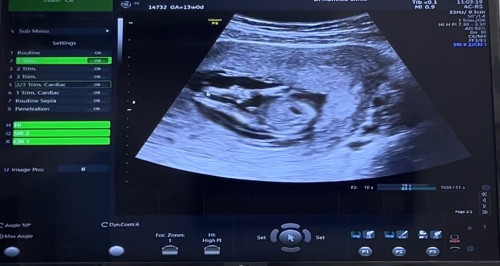

13 week คุณหมอบอกต้าวจิ๋วน่าจะเป็นผู้ชาย รู้ไวไปมั้ย แบบนี้ ผู้ชายแน่นอนมั้ยคะ 👶🏻💕

น้องผู้ชายดูง่าย 12วีคก็รู้เลยจ้า